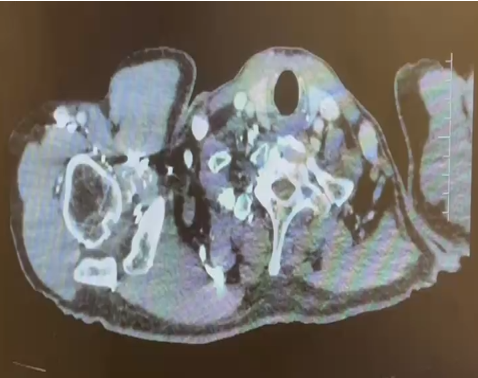

主诉:活动后气促 1 月余,检查发现右肾肿瘤并腔静脉 II 级瘤栓。

外院行穿刺活检:(右肾结节)穿刺活检,可见异型细胞,巢团状分布,局部肾实质见片状淋巴细胞浸润,可见肉芽肿性炎,免疫组化:2403798 -A01#:CK(pan)(+)、EMA(-)、Pax -8(+)、CA IX(+)、CK7(-)、CD10(-)、Vimentin(+)、p504s (+)、SDHB(+)、FH (+)、Melanoma(-)、CD117(-)、TFE - 3(个别弱 +)、Ki67(+,5-10%)。

结合免疫组化考虑肾细胞癌,倾向乳头状肾细胞癌,建议结合切除肿块病检进一步诊断,其中肉芽肿性炎的具体病原体类型请结合分子病理报告。

2024.1检查报告

CT 检查报告

1.左肺动脉主干及分支、右下肺动脉分支多发肺栓塞;

2.下腔静脉、右肾静脉及其属支、左肾静脉及左侧髂总静脉多发血检形成,请结合临床。

3.双肺散在炎症,双侧胸膜增厚;

4.右肾大片状低强化灶,请结合临床。

日期:2024.1.10

1.右肾上极稍低密度肿块灶及肾盂、输尿管上段壁明显增厚:考虑恶性病变,伴右肾静脉-下腔静脉-左肾静脉起始部癌栓形成可能性大,请结合临床。

2.右中肺外侧段肺动脉、左肺动脉干、左上下肺动脉多发栓塞。